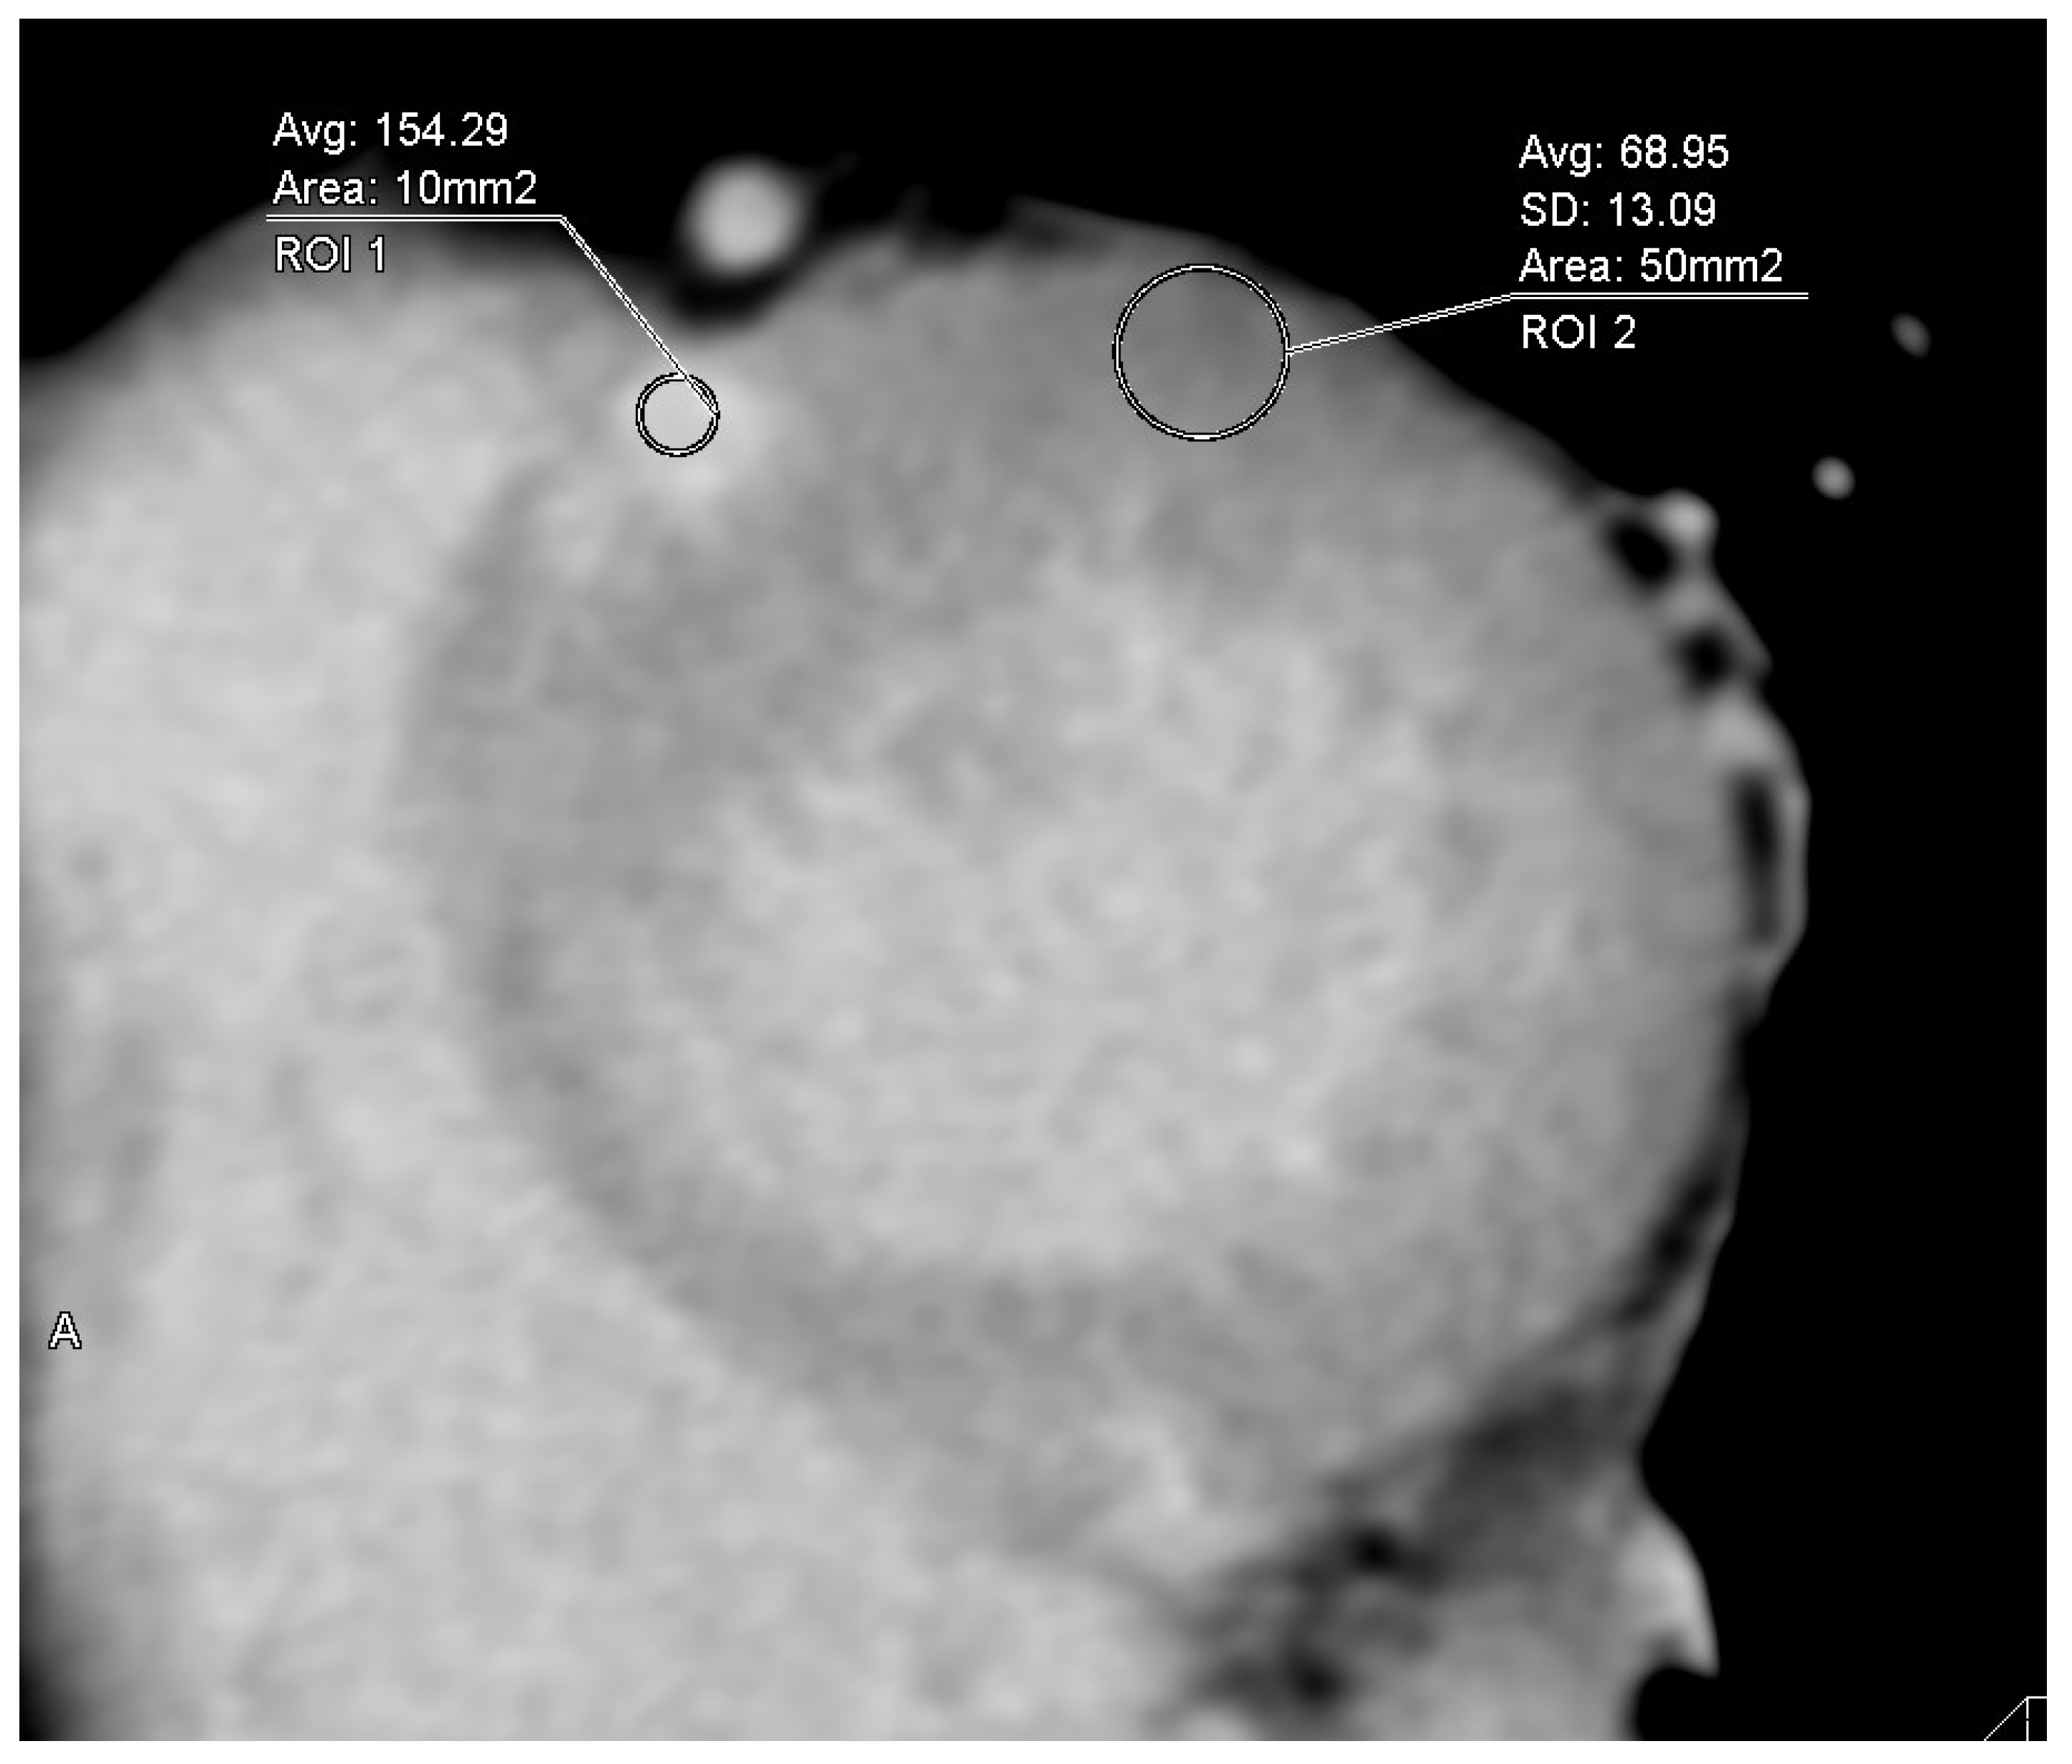

2.2. Analysis of Cardiac CT Images Including ECV

| ROI | Regions of interest |